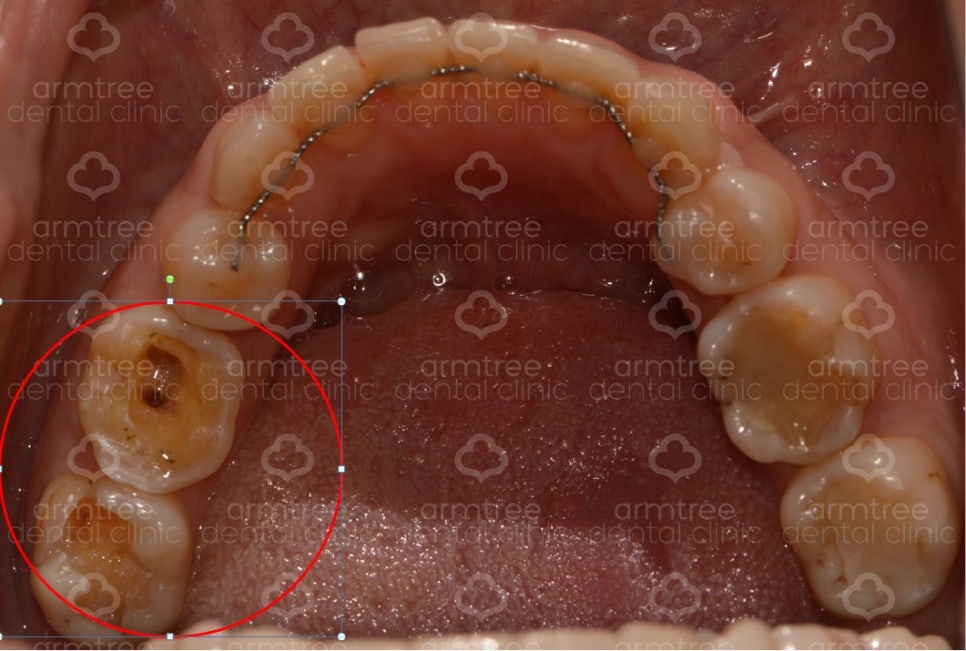

2번 사진] 환자의 구강 내 사진

환자분은 검사 결과 오른쪽 아래 6번과 7번 치아에 통증이 있었습니다. 그 치아로 인해 전체적으로 다 아픈 것처럼 느낀 것이었지요. 1번 사진 큰 엑스레이에 보시면 6번 7번 치아에 하얗게 예전에 치료한 흔적이 보입니다. 레진이라는 재료를 이용해서 충치 자리를 메꾼 것이지요. 그런데 아마 예전에 치료할 당시 충치가 크고 깊었을 것입니다. 충치가 깊으면 치료를 했어도 치아에게는 지속적인 자극이 될 수 있습니다.

이 환자분은 6번과 7번 모두 아파하셨기에 둘 다 신경치료를 할 수도 있었지만, 제 경험으로는 6번이 원인 치아이고, 7번은 연관통(6번으로 인해 같이 아픈 것으로 착각하는 것)이라고 판단되어 7번 치아는 건드리지 않고 6번 치아만 신경치료를 시작하였습니다.